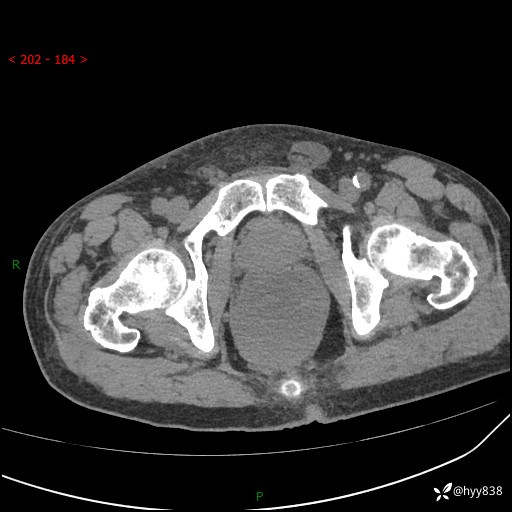

盆腔CT平扫+增强